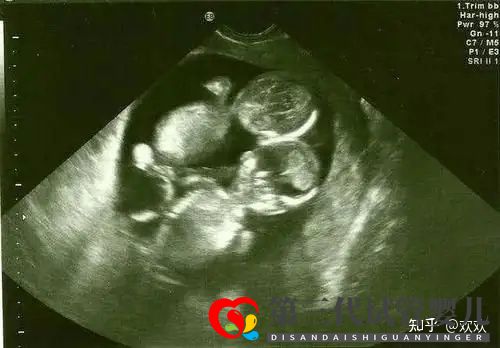

然后就是我再次來到了深圳進行移植了,移植過程是完全不痛的,在我印象里好像只有5分鐘吧,移植后醫生讓我平躺休息了將近2個半小時,也是根據我要求的,移植的雙胎,這次也是在這邊待了將近小半個月的,驗孕后才回家的,那個時候還不知道是不是兩個胚胎都著床了,到7周+B超,這個時刻我真的是刻骨銘心!聽到醫生說,2個寶寶都有心跳的那一刻,我又激動又感動!保佑后面都一路順順利利!寶寶健健康康的成長,可能是雙胎的原因現在的孕肚已經非常的明顯了,我還特意買了胎心檢測儀,平時總聽兩個寶貝的心跳生,希望我這一次雙胎N寶的好孕也能傳遞給您。